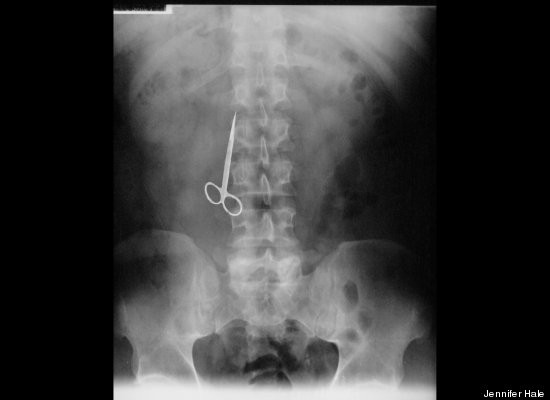

Điểm đặc biệt của cuốn sách là tập hợp 100 câu chuyện về những vật thể lạ bị kẹt một cách khó tin trong cơ thể. Ví dụ như cái kéo, cuộn dây điện hay búp bê Barbie.